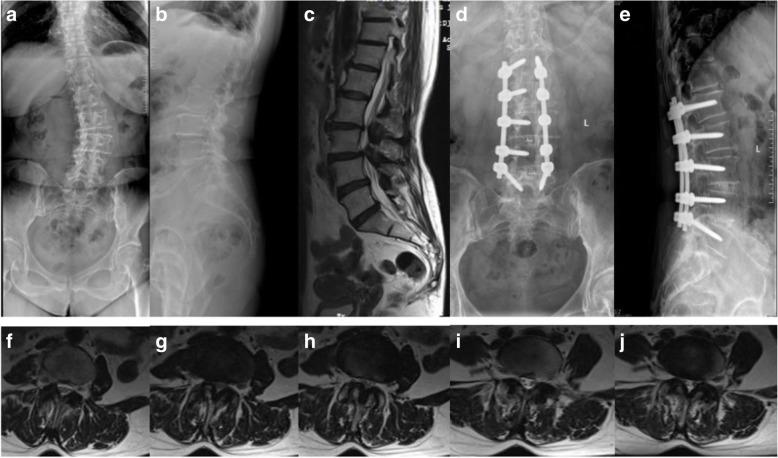

A retrospective study was performed on the clinical data of 71 patients with degenerative lumbar stenosis who underwent multi-level (at least 3 levels) posterior lumbar spinal fusion from January 2013 to December 2016. Two groups were divided according to lamina and posterior ligamentous complex (PLC) maintenance of proximal fixed vertebrae in surgery. In the 22 patients of group A, the proximal fixed vertebral lamina and PLC were not resected, and in the 49 patients of group B, the proximal fixed vertebral lamina and PLC were resected completely. Age, sex, body mass index (BMI), number of fixed vertebrae and fused levels, spinopelvic parameters, coronal Cobb angle, and modified Pfirrmann grading system were measured for each patient. A Cox proportional hazards model was used to analyze risk factors for upper ASD.

No symptomatic ASD was found during the follow-up period. Patients who underwent proximal fixed vertebral lamina and PLC resection had a significantly higher percentage of radiographic ASD (P = 0.042). The Cox proportional hazards model showed that age, sex, BMI, preoperative lumbar lordosis, sacral slope, pelvic tilt, coronal Cobb angle, number of fixed vertebrae, and interbody fusion levels had no significant differences for radiographic ASD. But a preoperative modified Pfirrmann grade higher than 3, a high degree of preoperative pelvic incidence, and more decompressed levels had statistical significance (P = 0.024, 0.041, and 0.008, respectively).

A preoperative modified Pfirrmann grade higher than 3, a high degree of preoperative pelvic incidence, and more decompressed levels might be risk factors for upper radiographic ASD after multi-level posterior lumbar spinal fusion surgery.